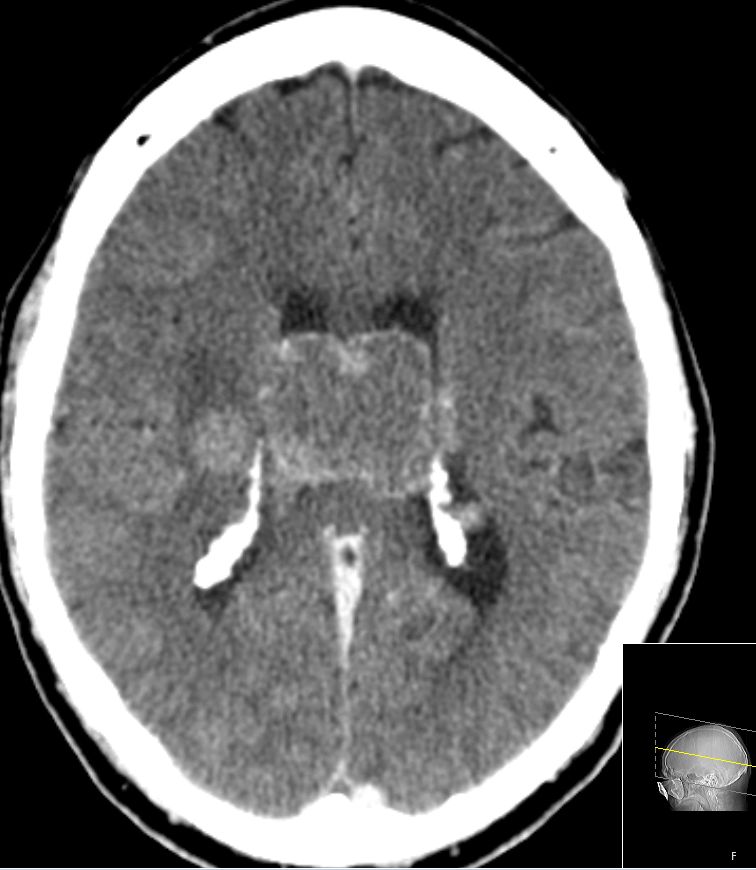

| zentrale Metastasen | 60-jähriger Mann, den vor einem Jahr ein

Plattenepithelkarzinom des linken Unterlappend cT2 pN2 Mo hatte. Nach 4x

Cisplatin-Vinorelbin und Bestrahlung vor 2 Monaten CR. Sturzes in der

Häuslichkeit eingewiesen werden. Jetzt Schwindel und zunehmende

Gangunsicherheit.

![]() |